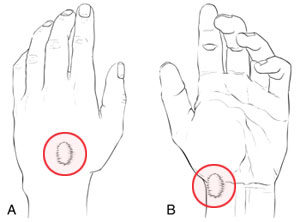

گانگلیونها بیشترین شیوع را در پشت مچ دارند و اغلب در افراد بزرگسال ( با هر سنی ) دیده می شوند. این گانگلیونها با شیوع کمتر در جلوی مچ یا کف دست و انگشتان نیز رخ می دهند. معمولا هیچ گونه علامتی بجز خود تورم و گاهی اوقات ناراحتی یا درد مختصر وجود ندارد .

تورم ممکن است نرم و کاملا کیستیک باشد , ولی اغلب سفت است. گانگلیونها اغلب با برجستگیهای استخوانی اشتباه گرفته می شود.ولی انجام معاینه دقیق تموج آنها را اثبات می کند .